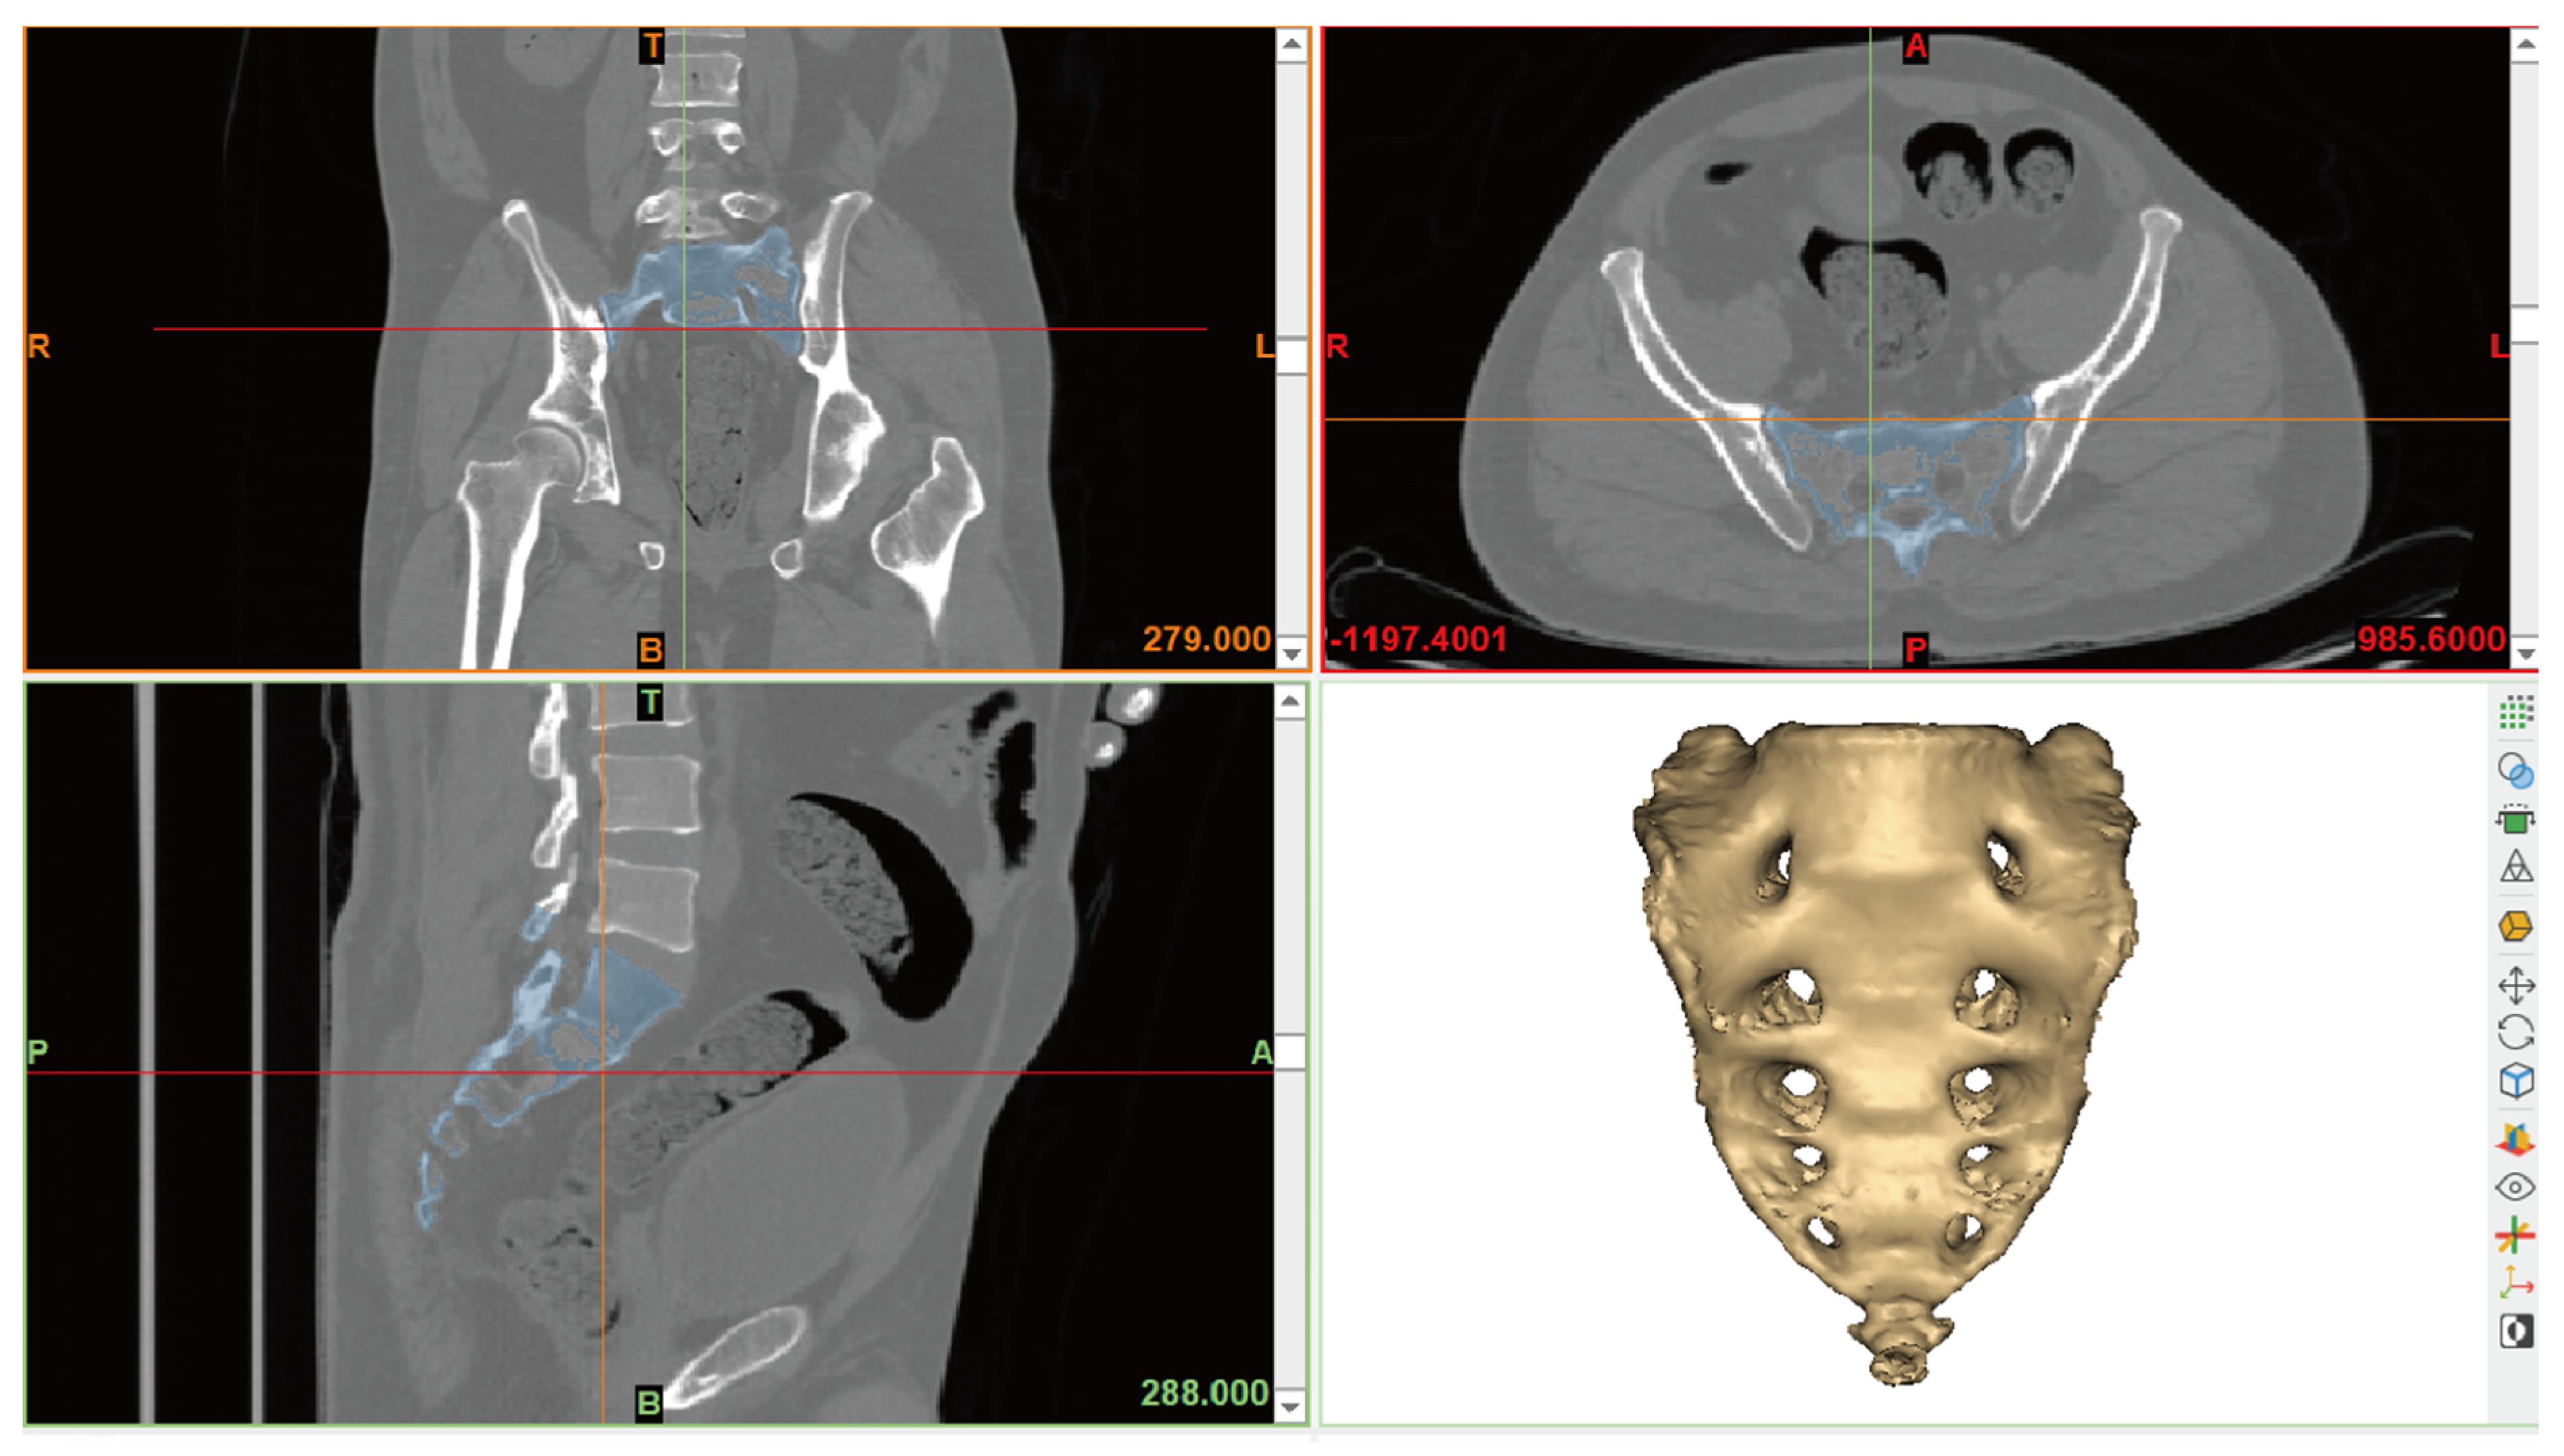

2.1. PMCT Image and Data Acquisition

2.2. Measurement of Sacrum Morphology

- SW (sacral width): Measured between the auricular surfaces at the posterosuperior point of the auricular surface.

- SL (sacral length): Measured from the upper midpoint of the promontory to the apex of the sacrum in the sagittal plane.

- SFD1 (sacral foramina distance of first): Measured between the left and right first anterior sacral foramina.

- SFD2 (sacral foramina distance of second): Measured between the left and right second anterior sacral foramina.

- SH1 (sacrum vertebrae height of first): Measured the height of the first sacral vertebra at the midline.

- SH2 (sacrum vertebrae height of second): Measured the height of the second sacral vertebra at the midline.

- SC (sacral curvature): Calculated as the quotient of the sacral anterior surface distance divided by SL.

- SI (sacrum index): Calculated as the quotient of SL divided by SW.